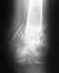

Re: Закрытый перелом лодыжек левой голени

Сустав пострадал необратимо. "Ряд реабилитационных мероприятий" не решит проблему. Сустав надо замыкать, т.е делать артродез.

Можно подумать об этндопротезировании, но тут преимуществ перед артродезом немного будет, это не тазобедренный сустав.

Артродез можно сделать практически в любом травматологическом отделении.